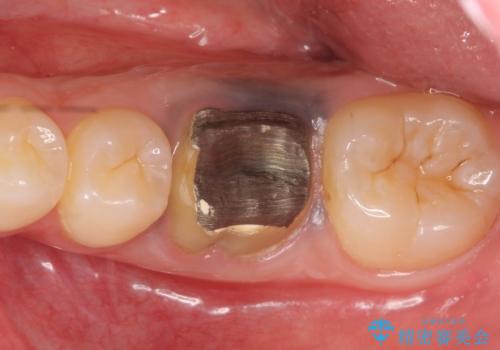

- 他院にて治療途中の歯を診て欲しいといらっしゃった方の症例です。

X線上で根尖病変を認めたため再根管治療を行い、オールセラミッククラウンによる補綴を行いました。